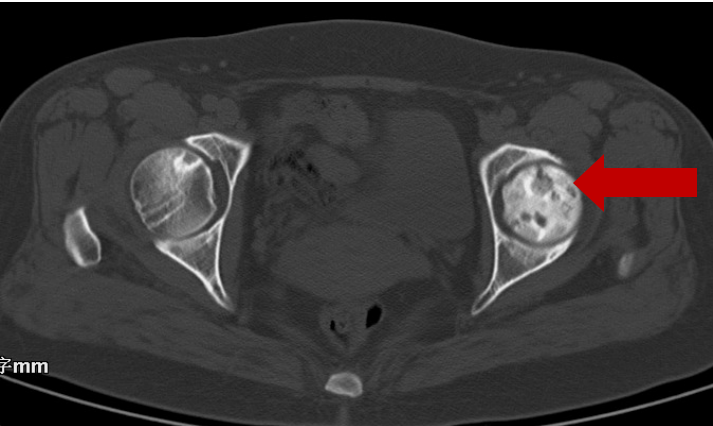

2020年8月6日CT:左股骨头囊样坏死区

分别于2020年8月7日、2020年10月12日行两次介入手术及相关米优最新版本综合治疗,左下肢酸痛不适消失,恢复正常生活。